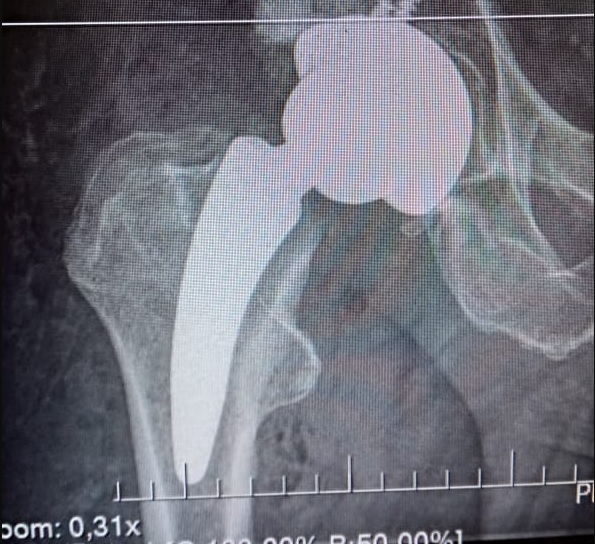

Con respecto a la prótesis, en Argentina comúnmente se usa una prótesis estándar que se coloca dentro del hueso del fémur, se trabaja en la parte central del hueso con raspas especiales. “La prótesis estándar es excelente, sin embargo la nueva que estamos usando es más chica e invade menos hueso. En donde innovamos es en hacer la combinación del abordaje anterior con la prótesis corta, cosa que no se había hecho en Argentina. Logramos un abordaje chico, poco doloroso, sin cortar músculo, invadiendo poco hueso, el paciente puede caminar al otro día y se puede ir a la casa. La diferencia es extrema”.

La principal ventaja de la prótesis de talle corto es que la cirugía mínimamente invasiva. «Se invade menos hueso, esto es muy importante porque las prótesis duran entre 15 y 20 años y luego hay que volver a operar y se pasa a utilizar una prótesis más larga, entonces hay que invadir más hueso para lograr mayor fijación. Si comenzamos usando la más corta, le ganamos años de vida al hueso del paciente», explicó López.

El equipo del CIAC lleva realizando 6 intervenciones con estas características, con materiales que son provistos exclusivamente en Salta por Magnus Corporation, una empresa líder con 60 años de experiencia en la venta de equipamiento hospitalario, insumos médicos, implantes quirúrgicos, de diagnóstico por imágenes, entre otros.